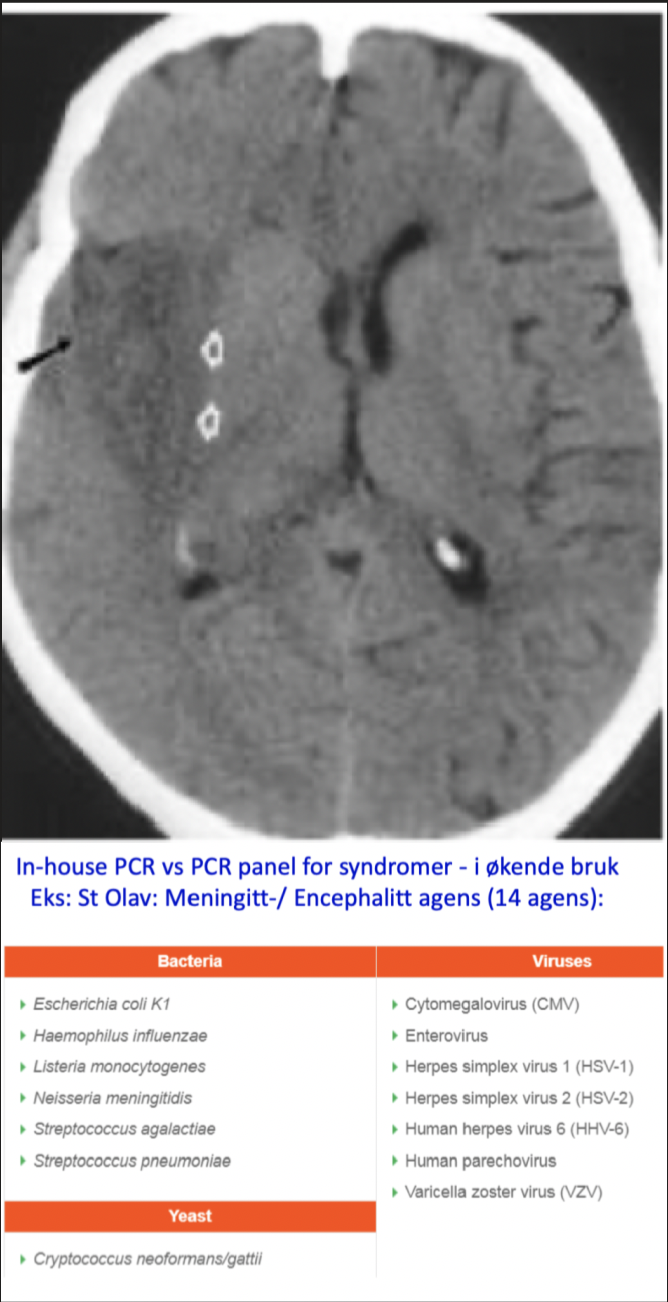

Hvordan stiller man encephalitt diagnostisk?

CSF:

- Lett pleocytose; primært mononuklære (MN)

- Protein; lett økning

- Normal glukose

Nevrodiagnostiske hjelpemidler:

- EEG

- CT/MR

Mikrobiologi

- Viruspåvisning; PCR, dyrkning av

- CSF, faeces, nasofarynxsekret

- Biopsi?

Serologi:

- Holdepunkter for intrathekal antistoff produksjon?

- Immunoglobuline ratio CSF : Serum

- IgM

- Titerstigning, alt. serokonversjon